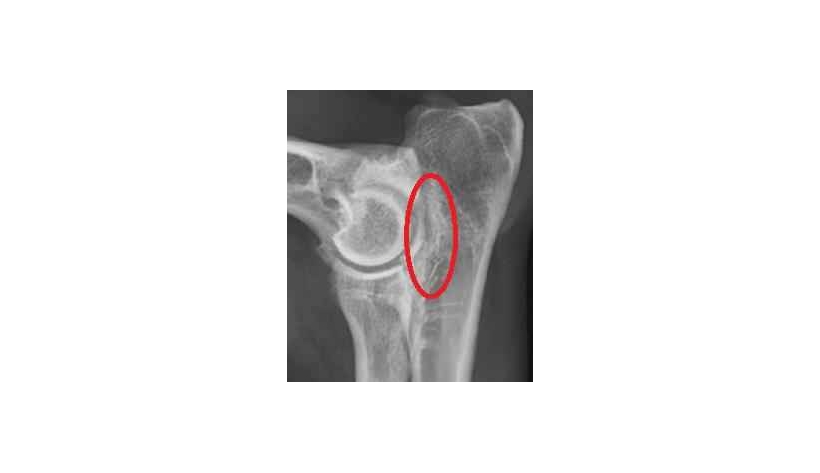

La fragmentation du processus coronoïde médial est souvent difficilement détectable directement. On observe cependant des lésions secondaires comme de la sclérose de l'os ulnaire (augmentation de la densité) et parfois des ostéophytes.

La fragmentation est souvent difficilement détectable directement. On observe cependant des lésions secondaires comme de la sclérose de l'os ulnaire (augmentation de la densité) et parfois des ostéophytes.